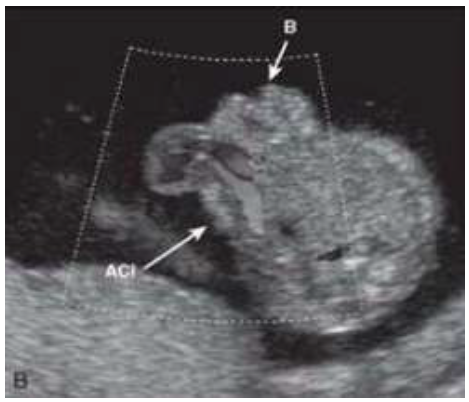

Paciente 24 anos, secundigesta, apresentando idade gestacional de 23 semanas, gestação não planejada, encaminhada para avaliação morfológica do segundo trimestre.

Após analisar as imagens abaixo, quais os sinais ecográficos encontrados e qual a hipótese diagnóstica?